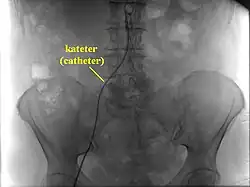

Katetr zavedený v oblasti pánve

Vedle diagnostických výkonů se angiografie používá i k výkonům terapeutickým: